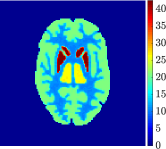

Figure 4, Figure 5, and Figure 6 show the mean images computed over the ten reconstructions obtained by the methods reg-AS-TR, reg-GN, and by the Matlab routine lsqcurvefit implementing a standard Trust-Region-Reflective least-squares algorithm [11, 10]. We used the noise-free IF and the perturbed IF with and of noise, respectively. Figure 7 contains mean and standard deviation values of the kinetic parameters computed over the ten reconstructions and over each one of the four homogeneous regions, for each one of the three noise levels on the IF.

In general, reg-AS-TR and lsqcurvefit seem to provide similar mean reconstructions, although uncertainties associated to lsqcurvefit are significantly bigger. On the other hand reg-GN seems to systematically underestimate the parameter values within region . Furthermore and as expected, for all methods the quality of the parametric reconstructions deteriorates with increasing noise levels; this is more clear from the and parametric images, probably due to the different sensitivities of the data with respect to the model parameters [37]. In reg-GN and lsqcurvefit some artifacts can be observed at the edges of the homogeneous regions, especially around region and region , whereas the effect of regularization in reg-AS-TR results in a reduced presence of artifacts while the structure of the regions is preserved. This general trend is confirmed by the error-bar plots of Figure 7. Finally, the frames in Figure 8 corresponding to reg-AS-TR show a significant improvement of the image quality with respect to what is provided by the other two approaches.